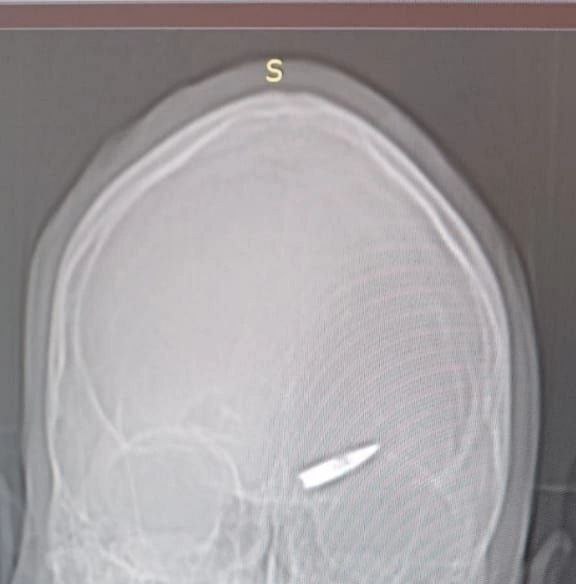

Морпех из 155 бригады МП РФ неделю воевал с пулей в голове.

Морской пехотинец с позывным «Шима» выполнял боевую задачу на Курском направлении. Во время боя его каску снесло с головы, и ему показалось, что пуля прошла по касательной. Боец продолжил выполнять боевую задачу, во время которой он получил осколочные ранения лица при взрыве вражеской гранаты. Позже он был эвакуирован и доставлен в госпиталь.

Находясь в госпитале врачи сделали ему рентген и были шокированы. На снимках была та самая пуля, которая неделю до этого попала в лоб бойца в районе левой брови, а он фактически даже не обратил на это внимания.